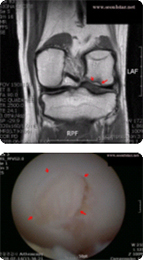

반월상연골 손상

수술전

수술

수술후

무릎 관절 속에는 무릎 위 뼈와 아래 뼈의 완충역할을 하는 반월상연골판이 있습니다. 이 판은 축구, 스키 등 무릎 부하가 많은 운동을 할 때 충격을 받아 자주 다치게 됩니다.

가끔은 특별한 원인 없이 찢어지기도 합니다. 방치하거나 치료가 늦어지면 연골판의 완충 역할이 없어진 채로 활동하게 돼 퇴행성관절염이 빨리 진행됩니다.

손상이 심하면 반월상연골이식술을 받아야 하지만 그 정도는 아닌 경우에 관절내시경을 이용해 치료할 수 있습니다.

관절내시경수술로 손상된 연골판 부위를 제거하거나 파열된 부위를 봉합하는 등의 치료가 가능합니다.